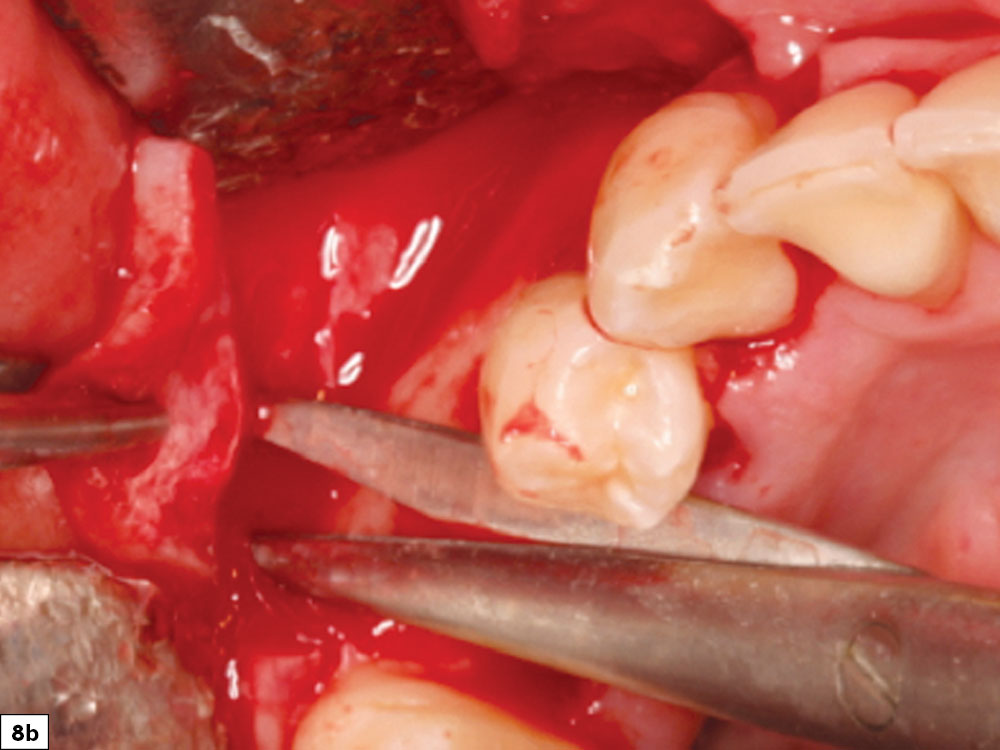

Flap tension is reduced by releasing the periosteal layer, allowing the elastic fibers of the underlying flap to stretch as the flap is drawn over the graft site. Stretching the tissue may be completed by either periosteal release incisions (shallow incisions with a scalpel blade in the periosteum) or a blunt dissection (Metzenbaum scissors placed into the periosteal tissue layer and opened, resulting in stretching of the tissue fibers). Ideally, extension of the flap should extend at least 5 mm beyond the edge of the adjacent margin after the flap is released (Figs. 8a, 8b).

Periosteal release incisions with a No. 15 blade

Broadbased tissue release with Metzenbaum scissors

Figures 8a, 8b: Periosteal release incisions with a No. 15 blade (8a), and broadbased tissue release with Metzenbaum scissors (8b).